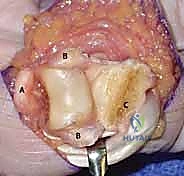

* *TECH FIG 1 • A. Brunner incision. The incision is made